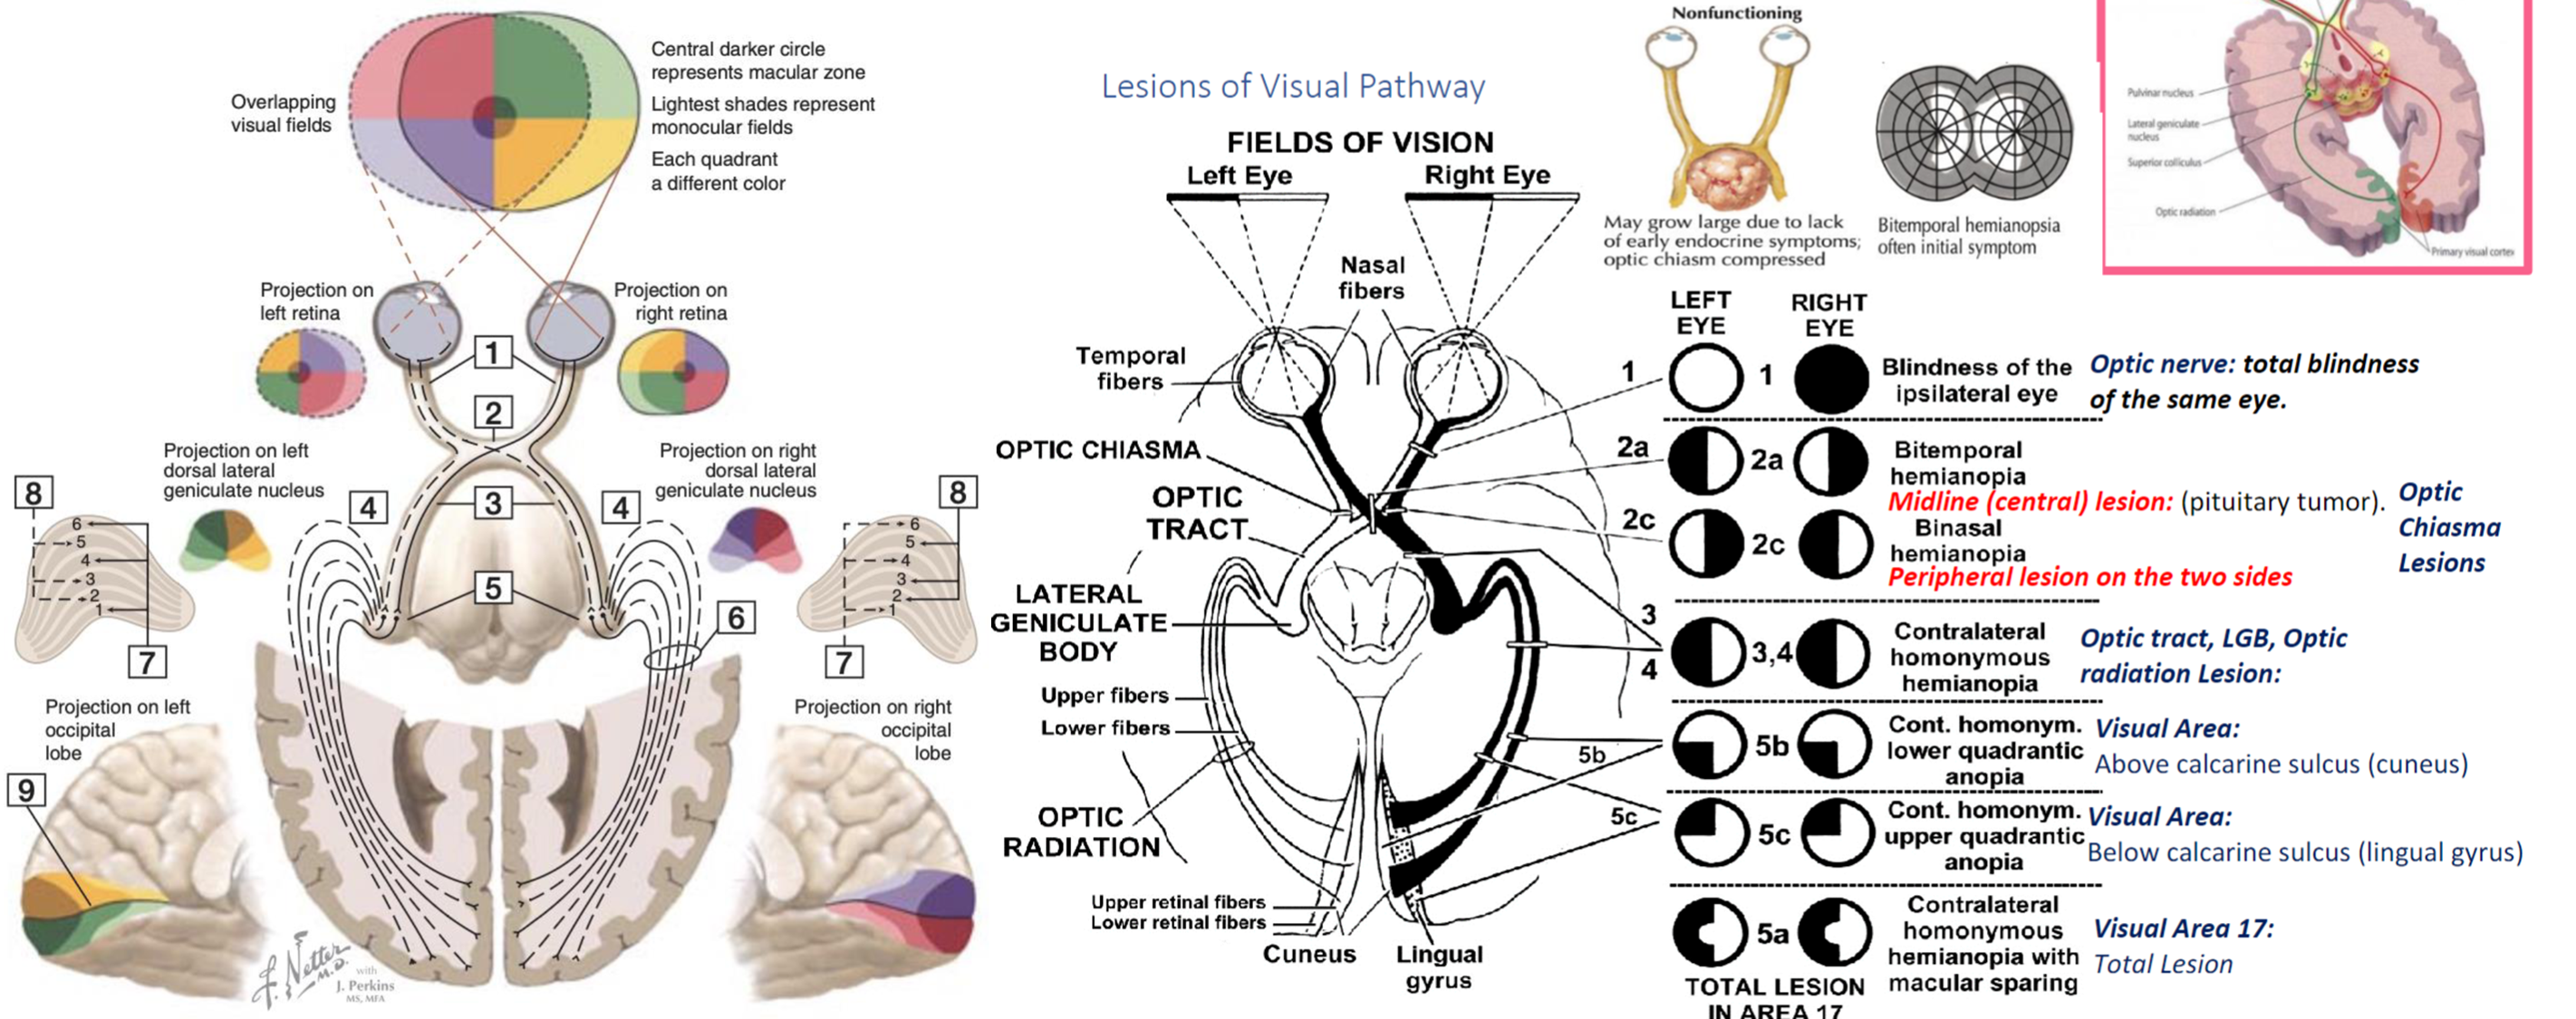

CN II - Optic Nerve

Disease that effect it: - Multiple Sclerosis - Diabetes - Pituitary Tumor

Examination - Visual acuity - (snellen chart) - 6 meters, if negative, test with numbers of fingers, then movement of hand, then light stimulation otherwise the patient is light blind. - Ischehara test - Color blindness related conditions; (X-Linked, Digoxin or anti-tuberculosis; Ethambutol) - Visual Field - Confrontation test - stay in same level to the patient, test one eye, close the other same as you - let the patient stare at your eyes without any movement. pull your finger towards center to confirm first sight with finger shaking, use your visual field as reference point. - testing temporal outer and nasal from central

Its important to know diseases related to the damaged lesion; Aforementioned in this graph